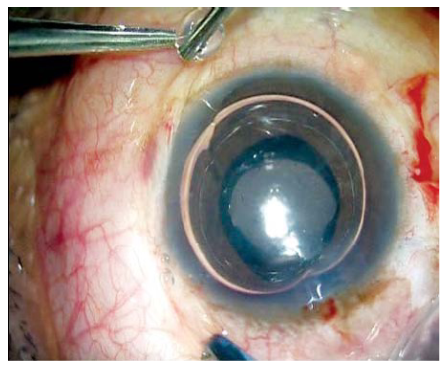

在IOL襻的理想出口处进行巩膜局部切除和电灼。插入灌注套管或前房维持器。如果使用灌注套管,可以使用23G无缝线的穿刺器和导管。灌注套管最好位于鼻下内侧象限,以防干扰巩膜瓣的制作。制作两个大约2.5mm×3 mm的巩膜瓣,对角相距180度(图 1A 和 B)。然后通过玻璃体腔或前路进行23G玻璃体切割术,以解除所有玻璃体牵拉。在巩膜瓣下,大约离角膜缘1.0mm处进行两个直的巩膜切口。然后制作一个透明的角膜/巩膜隧道切口以植入IOL。IOL植入时,术者一手使用McPherson钳,另一手使用23G/25G的夹持钳(Micro Surgical Technology, USA)通过下方巩膜切口。可以使用任何末端开口的镊子,夹住IOL襻的尖端,沿着襻的曲线穿过下方的巩膜切口并将其拉出(图2A和B),使其在下方巩膜瓣下露出。同样,通过巩膜瓣下的上方巩膜切口,也可以将襻的尾端露出。如果制作的是巩膜隧道切口,用10-0单丝尼龙线缝合切口。然后将襻的尖端塞入用26G针制作的巩膜隧道的延伸点中。用纤维蛋白胶闭合巩膜瓣(图3A和图B)。移除前房维持器或灌注套管。结膜也用相同的纤维蛋白胶闭合(图4)。

图3A和B:重组纤维蛋白胶在襻上巩膜瓣下注射,后封闭巩膜瓣。